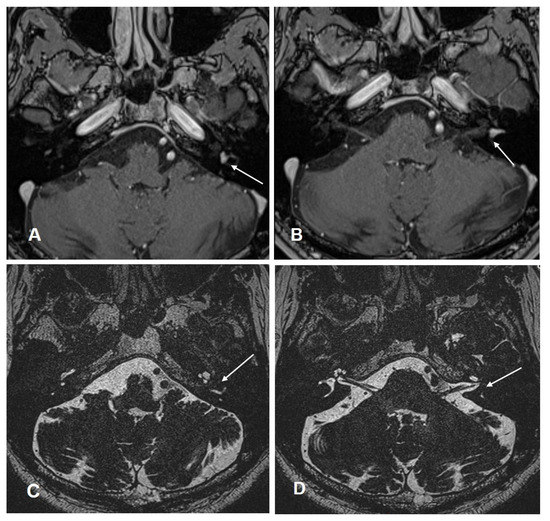

Patient #3 had a middle cochlear turn ILS (Figure 3) requiring subtotal cochleoectomy, meaning that parts of the modiolus had to be removed. One year after ILS removal and cochlear implantation, this patient scored 50% in FMT.

Figure 3. Case #3: ILS of the middle cochlear turn (A) MR image T1 VIBE with i.v. gadolinium: the white arrow points to the intracochlear schwannoma in the middle turn. (B) Intraoperative image of the subtotal cochleoectomy exposing the schwannoma (black arrow) in the middle turn. (C) Magnified image of the intracochlear schwannoma in the middle turn (black arrow). (D) Postoperative ConeBeam CT of the CI electrode (white arrow) in the cochlea.